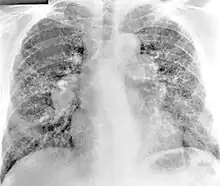

Diagnosis of berylliosis is based on history of beryllium exposures, documented beryllium sensitivity, and granulomatous inflammation on lung biopsy. Given the invasive nature of a lung biopsy, diagnosis can also be based on clinical history consistent with berylliosis, abnormal chest x-ray or CT scan findings, and abnormalities in pulmonary function tests.[16]

Chest radiography findings of berylliosis are non-specific. Early in the disease radiography findings are usually normal. In later stages interstitial fibrosis, pleural irregularities, hilar lymphadenopathy and ground-glass opacities have been reported.[20][21] Findings on CT are also not specific to berylliosis. Findings that are common in CT scans of people with berylliosis include parenchymal nodules in early stages. One study found that ground-glass opacities were more commonly seen on CT scan in berylliosis than in sarcoidosis. In later stages hilar lymphadenopathy, interstitial pulmonary fibrosis and pleural thickening.[21]